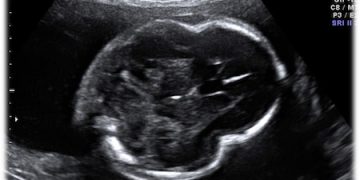

Caso del Mese di Dicembre 2021

Cari soci, finalmente la soluzione del caso del mese di Dicembre! Scarica il File L'attesa è finita: Al seguente link la...